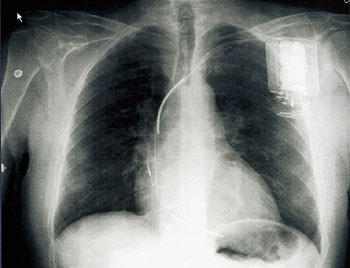

De siste ti årene er implantasjon av defibrillator blitt et etablert behandlingstilbud til pasienter som har høy risiko for sirkulasjonsstans og plutselig død som følge av alvorlige rytmeforstyrrelser i hjertekamrene. Implanterbar defibrillator kan ikke hindre rytmeforstyrrelser i å opptre, men apparatet er i stand til å registrere og stanse arytmien automatisk i løpet av noen få sekunder, og dermed beskytte personen mot hjertestans.

Anslagsvis 5 000 nordmenn rammes hvert år av plutselig hjertedød, mange uten å ha hatt varselsymptomer. I de fleste tilfellene skyldes sirkulasjonsstansen enten ventrikkelflimmer eller rask ventrikkeltakykardi, og de fleste som dør har koronarsykdom eller kardiomyopati.

Et mindretall overlever hjertestans utenfor sykehus, men 15–40 % får ny hjertestans innen to år.